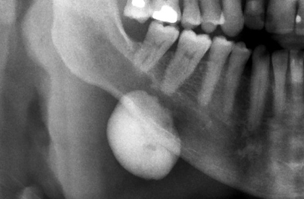

osteoblastoma

notice it is >2cm